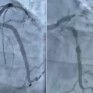

مستشفى الحبيب بالخبر ينقذ حياة مراجع توقف قلبه بسبب انسداد كلي للشريان النازل

الواحة نيوز

10:29 ص - 3 ديسمبر، 2025